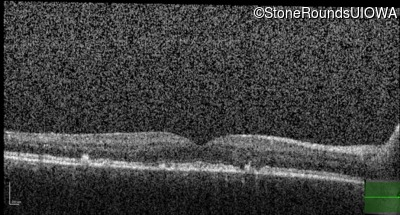

Age at visit: 49 years

This 49 year old man was first told he had a fundus abnormality on a routine eye exam at age 34. Ten years later he noticed some distortion just superior to fixation.

Age at visit: 49 years (Visit 2)

Pattern Dystrophy PRPH2 Gln239Stop CAG>TAG   AD